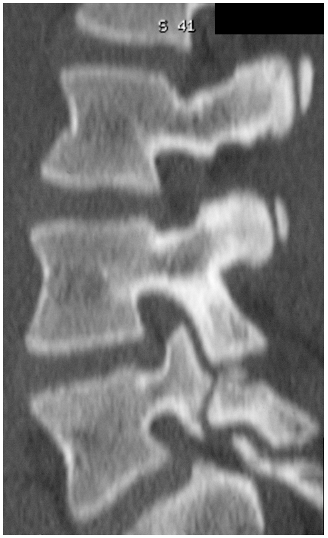

The single-photon emission computerized

tomography bone scan has been shown to be the best study for detecting

early pars stress injury (Fig. 5-6). -

Focal computed tomography (CT), is

necessary to examine the metabolically active areas to ascertain

whether fracture or stress reaction is present and to document healing

after treatment (Fig. 5-7).

Figure 5-6

Single-photon emission computerized tomography bone scan demonstrating increased uptake at pars interarticularis. A hot bone scan indicates increased metabolic activity with or without a visible fracture. A cold bone scan does not preclude a long-standing quiescent pars fracture. |

Figure 5-7

Focal CT is used to assess whether there is a visible fracture or simply prefracture stress reaction. It is also used to assess progressive healing. |